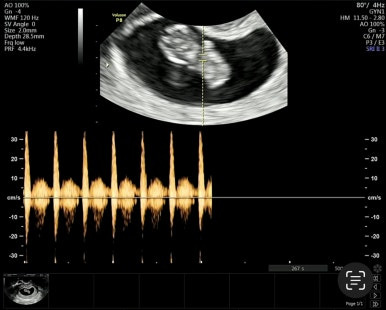

9주 1일차

젤리곰 같은 태아를 볼 수 있다! 벌써 손발이 생겨 움직이는 모습이 너무 신기하다.

이 시기는 평소보다 심장이 원래 빨리 뛰는 시기이다.